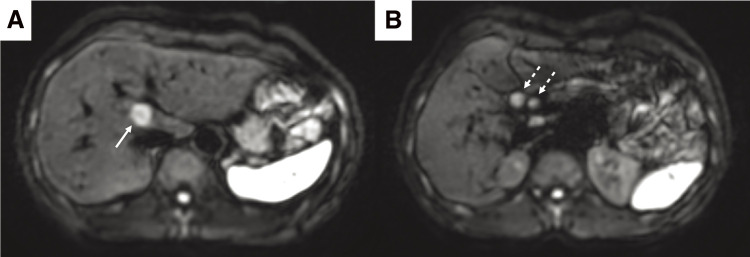

Case presentation: A 52-year-old woman was referred to our hospital and was subsequently diagnosed with bilateral breast cancer. Computed tomography (CT) and magnetic resonance imaging incidentally detected a liver tumor in the hilar region and lymph node enlargement in the hepatoduodenal ligament. A 19 mm tumor was observed in the area surrounded by the right and left branches of the portal vein and an abnormal portal branch of segment 7. Positron emission tomography-CT showed fluorodeoxyglucose uptake in the liver tumor, hepatoduodenal ligament lymph nodes, and bilateral breasts. A tumor biopsy showed a papillary tumor, and ICC was suspected. As ICC with LNM has a poor prognosis, neoadjuvant chemotherapy was planned. Genetic testing using a blood sample revealed a BRCA2 mutation, indicating the patient would benefit from chemotherapy, particularly cisplatin. The patient received a chemotherapy regimen comprised of gemcitabine, cisplatin, and S-1 (GCS), and after 7 courses, her carbohydrate antigen 19-9 level decreased from 2433 to 15 U/mL. CT showed that the tumor had shrunk and the LNMs were indistinct. The patient was referred to our department for curative surgery, which included a left hepatectomy, caudate lobectomy, hepatoduodenal ligament lymph node dissection, bile duct resection, and choledocojejunostomy. The postoperative course was generally uneventful, and the patient was discharged on postoperative day 18. Pathological examination of the resected specimen revealed an absence of malignant cells. At 24 months postoperative, there was no evidence of recurrence.